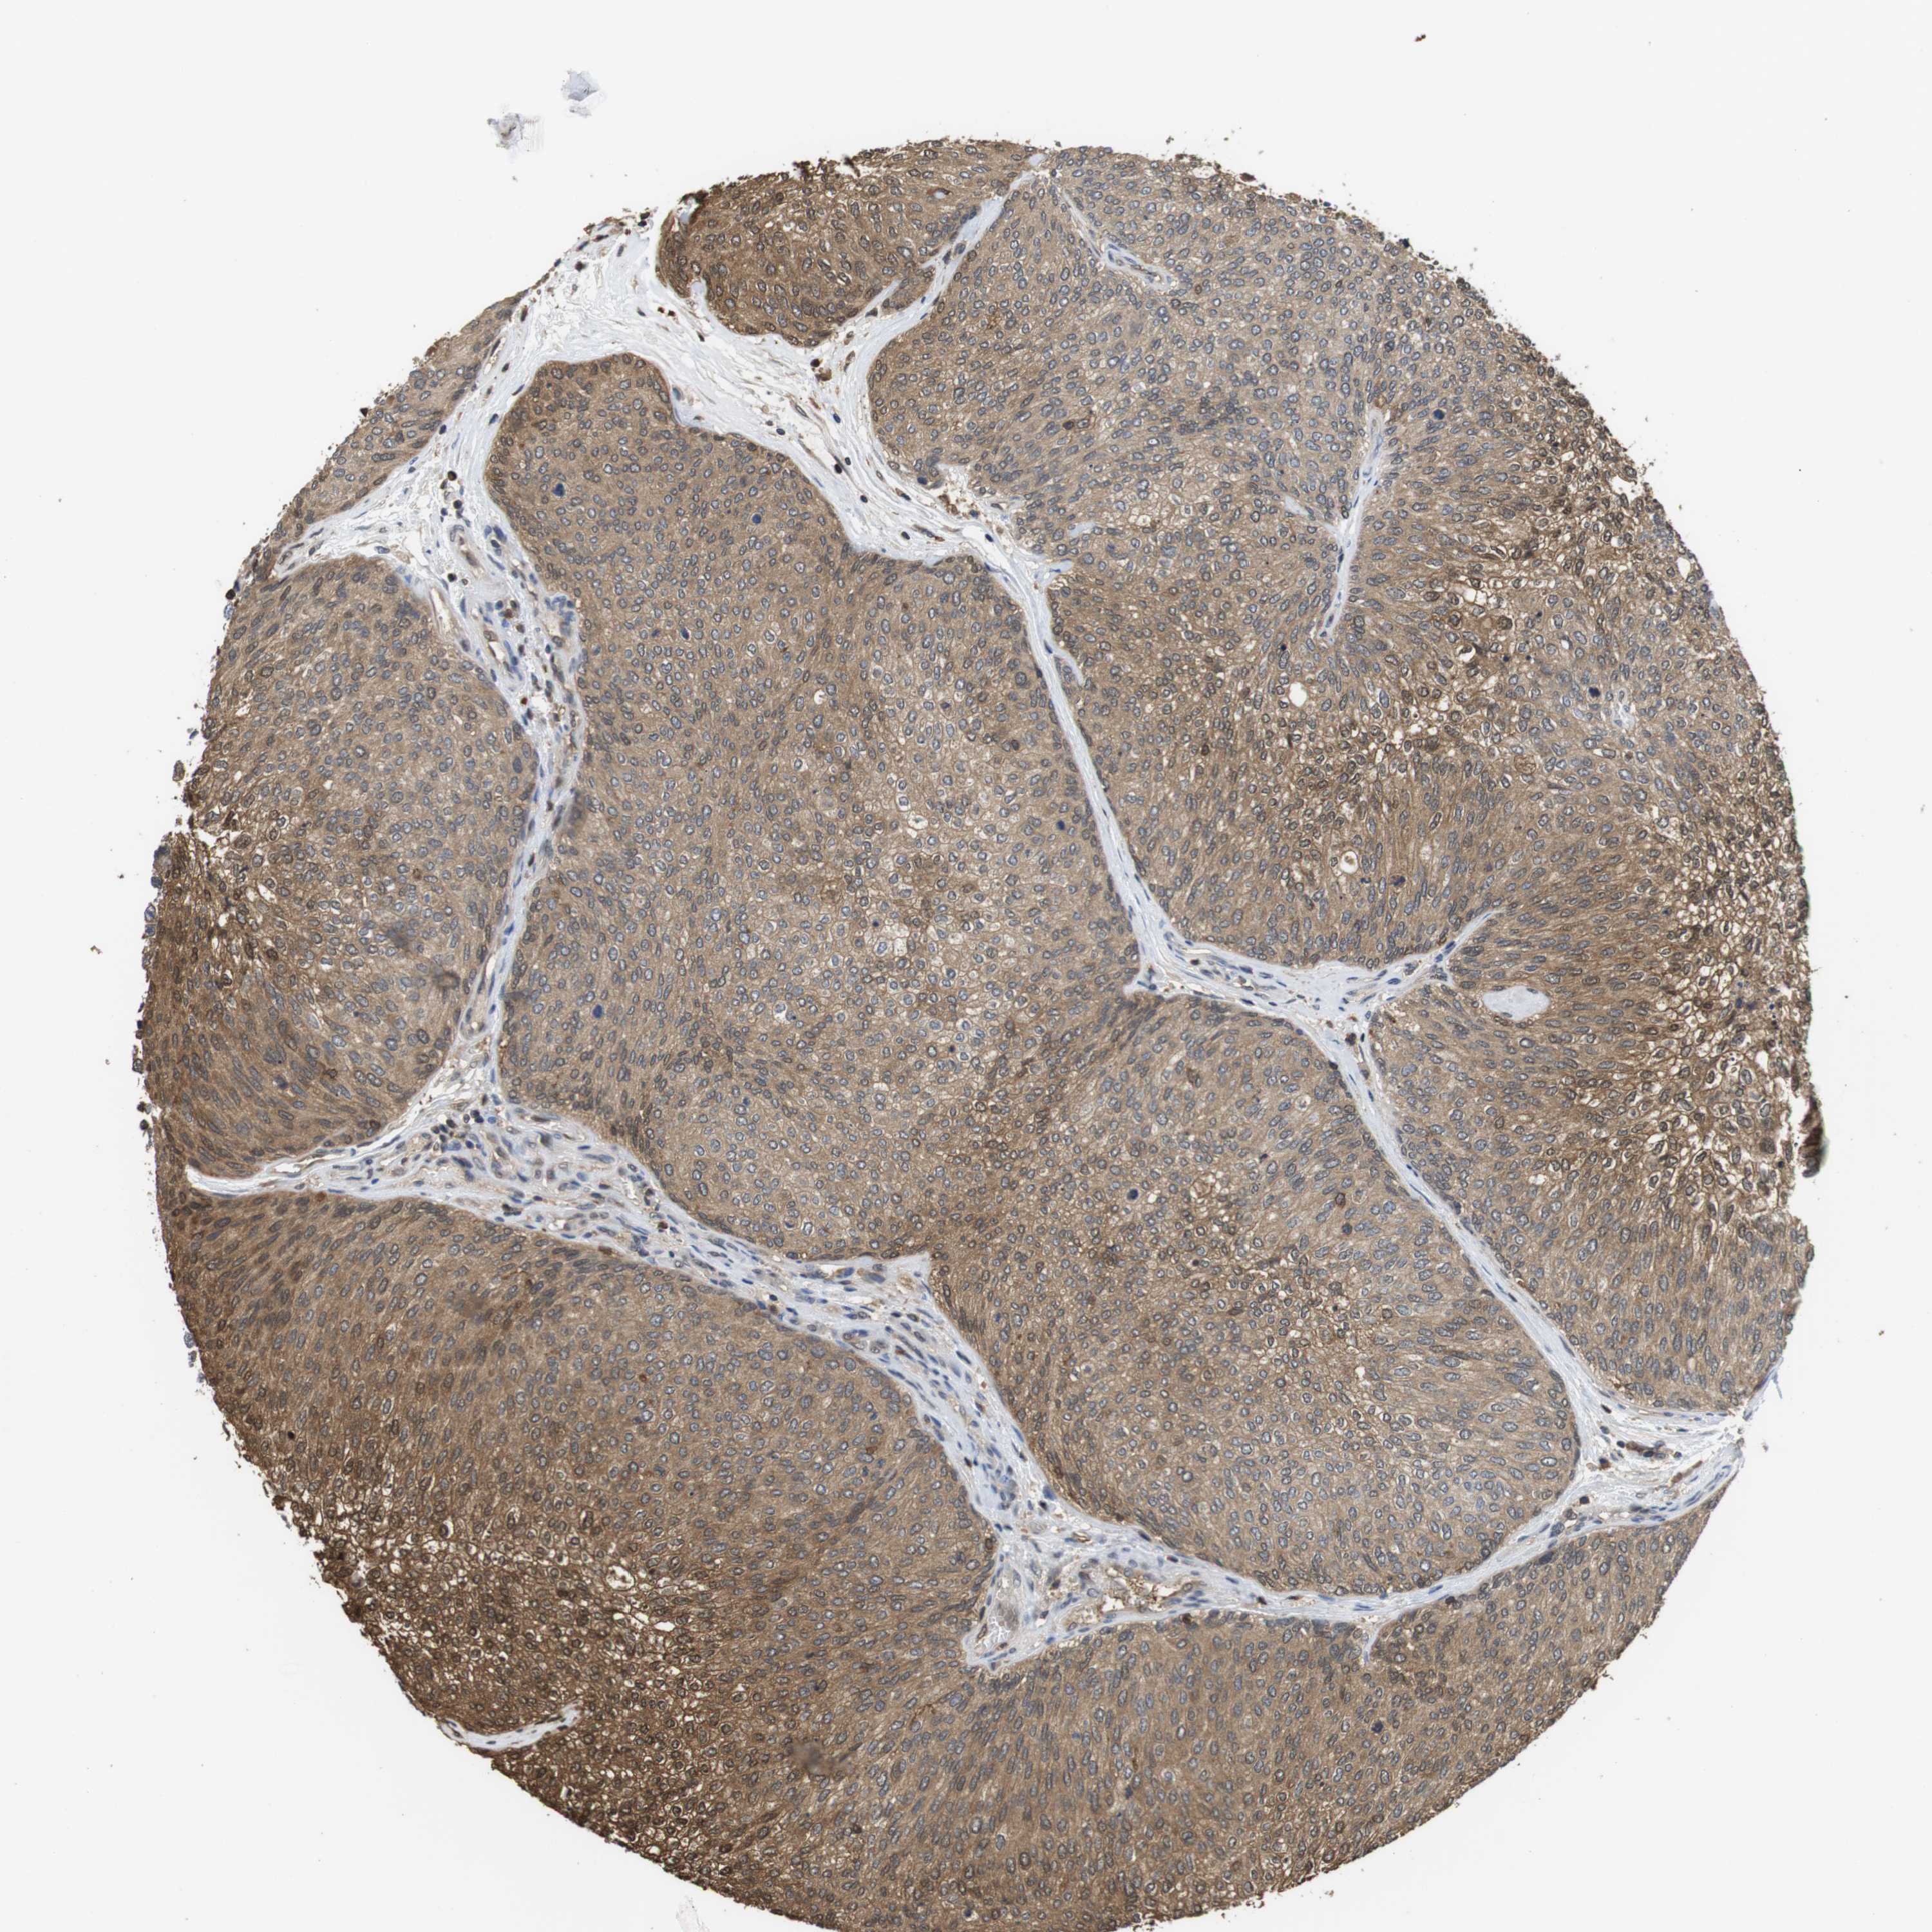

UROTHELIAL CANCER - Protein expressioni

A mouse-over function shows sample information and annotation data. Click on an image to view it in a full screen mode. Samples can be filtered based on level of antibody staining by selecting one or several of the following categories: high, medium, low and not detected. The assay and annotation is described here.

Note that samples used for immunohistochemistry by the Human Protein Atlas do not correspond to samples in the TCGA dataset.

Antibody stainingi

Antibody staining in the annotated cell types in the current human tissue is reported as not detected, low, medium, or high, based on conventional immunohistochemistry profiling in selected tissues. This score is based on the combination of the staining intensity and fraction of stained cells.

Each image is clickable and will lead to virtual microscopy that enables deeper exploration of all samples and also displays staining intensity scores, fraction scores and subcellular localization as well as patient and tissue information for each sample.

Antibody CAB015336

Antibody CAB069404

Staining

High

Medium

Low

Not detected

Intensity

Strong

Moderate

Weak

Negative

Quantity

>75%

75%-25%

<25%

None

Location

Nuclear

Cytoplasmic/membranous

Cytoplasmic/membranous,nuclear

Urothelial carcinoma, Low grade